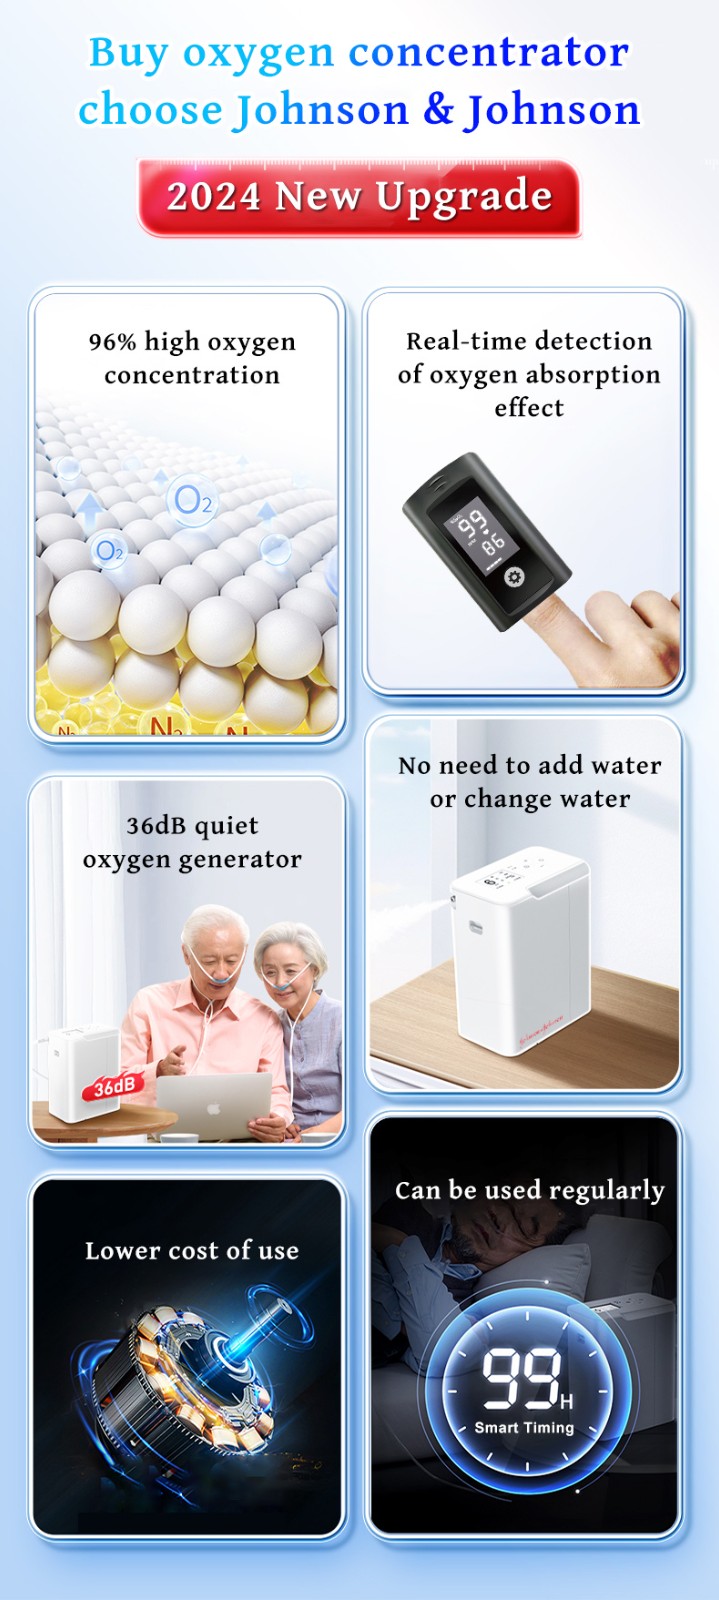

Ο συμπυκνωτής οξυγόνου που πουλάμε είναι ένα προϊόν που αναπτύξαμε μετά από 5 χρόνια έρευνας και ανάπτυξης. Μετά την κυκλοφορία του, έλαβε ομόφωνους επαίνους από αμέτρητους αναπνευστικούς ασθενείς και πουλήθηκε σε εκατοντάδες χώρες σε όλο τον κόσμο.